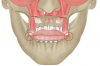

Fig 12. Illustration showing the maintenance of the muscle suspension using minimally invasive approach.

Figure 12